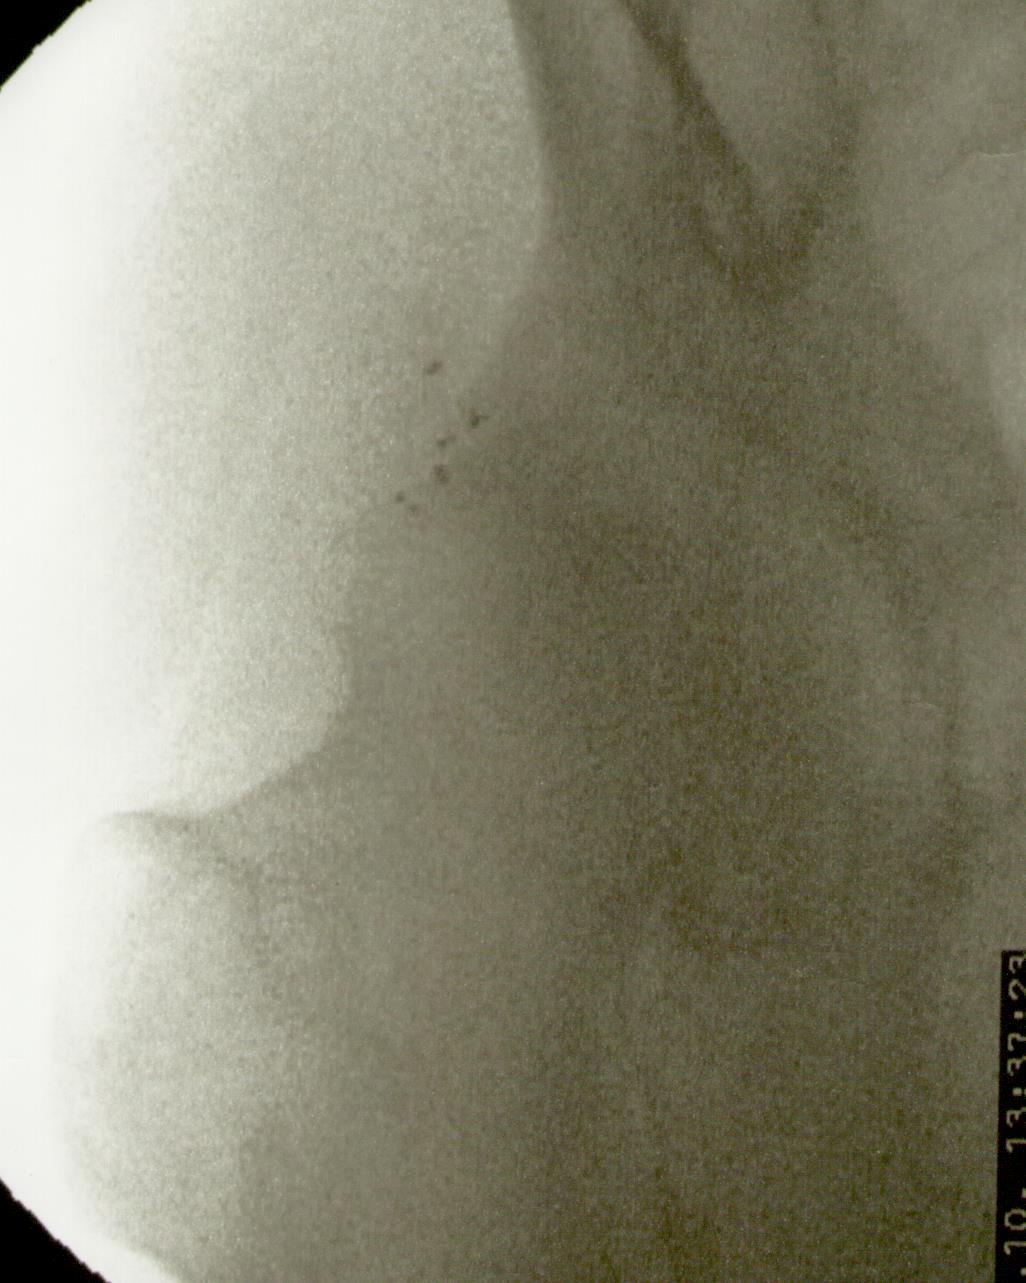

Más abajo se observarán unas imágenes de casos de implantes de oro en cadera